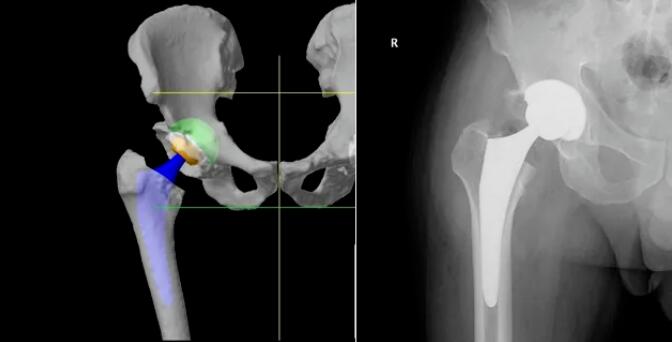

利用患者术前CT数据构建3D骨骼模型,通过导航模块在专属3D模型图像上规划植入物尺寸与摆放位置,对安装效果和截骨量、截骨角度等进行提前“预演”,实现精准术前方案定制。

手术中系统实时捕捉软组织张力,关节面的接触点,髋关节的前倾角,下肢长度,旋转中心,偏心距等临床信息,医生据此调整手术计划,实现关节平衡并达到1度1毫米个性化放置。当操作偏离预设路径0.1毫米,机械臂触发阻力反馈、警报并终止操作。

借助限制性立体定位边界与三维可视化截骨界面,独有的反馈式机器臂辅助医生实现精准截骨与假体精准安放。患者不仅恢复更快、使用体验更佳,同时有效降低磨损率与并发症,延长假体使用寿命,让“一次置换用终生”成为可能!